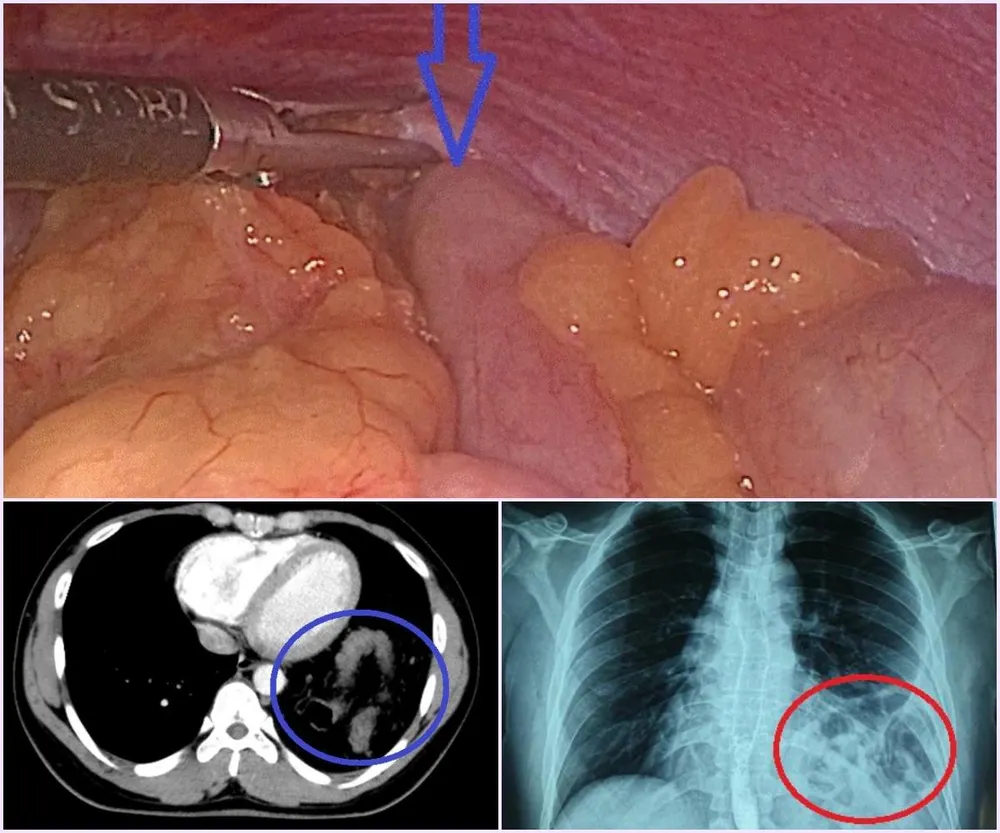

Hình ảnh đại tràng chui lên khoang phổi của nam thanh niên. |

Tại BV Bạch Mai, bệnh nhân được chỉ định chụp X-quang ngực và được phát hiện tình trạng có hình bóng hơi của ruột ở trên ngực trái.

Bệnh nhân được hoàn thiện thêm các xét nghiệm cận lâm sàng và hội chẩn thêm các chuyên khoa, chụp cắt lớp, khẳng định có thoát vị tạng bụng qua cơ hoành lên ngực trái. Sau đó, bệnh nhân được chuyển Khoa Phẫu thuật tiêu hóa - gan mật tụy để phẫu thuật sửa tổn thương và phục hồi cơ hoành.

Trong lúc mổ, BS thấy gần toàn bộ đại tràng ngang, lách, dạ dày và mạc nối lớn đã chui qua cơ hoành lên khoang màng phổi bên trái. Sau khi đưa các tạng trên trở lại ổ bụng, tổn thương cơ hoành bên trái lộ rõ là một lỗ rộng khoảng 6x8 cm.

Đây chính là nguyên nhân gây ra thoát vị, kết hợp với tiền sử có chấn thương, chẩn đoán trong mổ là thoát vị hoành trái do vỡ cơ hoành. Cơ hoành vỡ đã được các phẫu thuật viên khâu phục hồi kín, ca mổ diễn ra trong 1 giờ 30 phút.